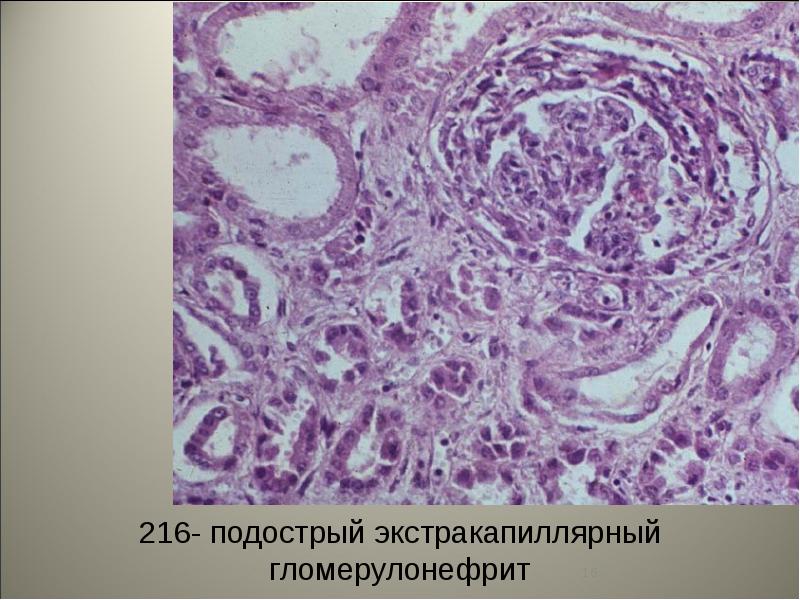

Механизм остро го диффузного гломерулонефрита